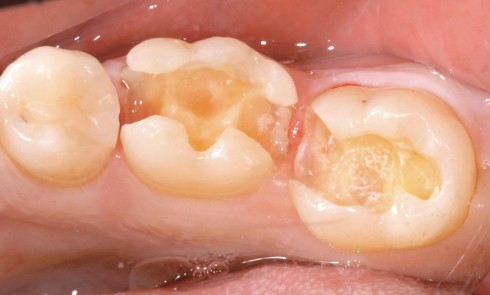

Odontologie restauratrice

Article réservé à nos abonnés Estimer l’état pulpaire

L’abandon des principes mécanistes de Black au profit d’une dentisterie a minima basée sur la préservation tissulaire couplée aux progrès...

Article réservé à nos abonnés Inlays et onlays en céramique : critères de succès

Avant le développement des systèmes adhésifs il y a une trentaine d’années, les restaurations indirectes au niveau des secteurs latéraux...